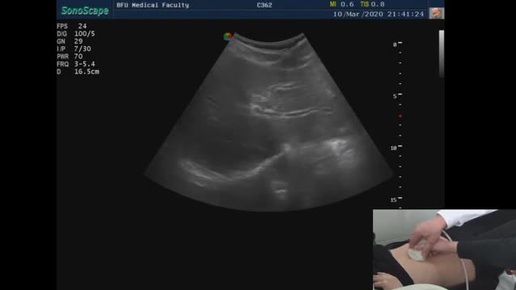

УЗИ печени практикум

УЗИ обучающие видео